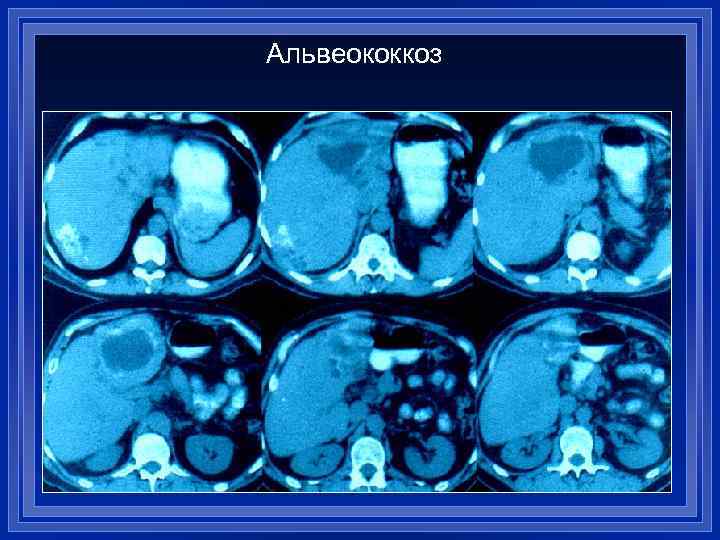

Альвеококкоз